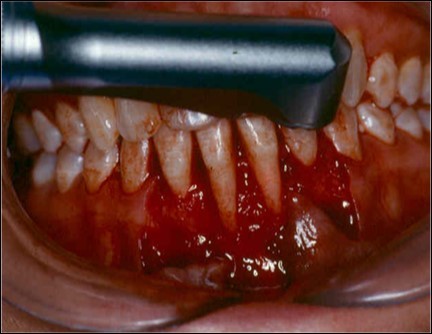

The patient under hard emotional stress that associated with bacterial plaque promoted ANUG with necrosis of alveolar bone and marginal gingival soft tissue in 31 and 41 (Figure 1). The patient was free of systemic disease and was not currently receiving any medication. Initial therapy was carried out using Er-YAG laser, to promote scaling and root planning and oral hygiene instruction. After initial therapy (Figure 2) the surgical method employed consists of the following steps as described by Langer and Langer5.

Figure 2.After initial therapy

A partial thickness flap is created with two vertical incisions placed at least one-half to one tooth wider mesiodistally than the area of gingival recession. The coronal margin of the flap is started with a horizontal sulcular incision to preserve all existing radicular gingiva. The interproximal papillae are left intact. The flap dissection is partial thickness leaving connective tissue over the existing bone and / or root surfaces. The root of the involved tooth is carefully scaled and planed until its surface is smooth and hard. Er-YAG laser is then applied to its surface to promote root biomodification, at powers ranging from 25 to 50 mJ/pulse/sec. (Figure 3, Figure 3A).